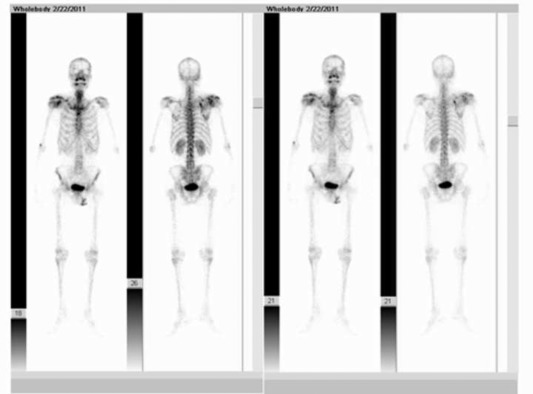

Laboratory tests showed that the serum concentration of CEA reached 17.64 ng/ml. Imaging: X-ray (Fig. 1 a) showed the destruction of the right scapula, and a shadow of soft tissue mass in right scapular region; CT (Fig. 1 b) showed right scapula destructed, surrounded by irregular low-density mass shadow. MRI (Fig. 1 c, d) showed a shadow of soft tissue mass inside of right shoulder, two rounded nodule below the right clavicle, considering as a malignant tumor of the right scapula, right subclavian lymph node metastasis. Emission computed tomography (ECT) showed high metabolism activity in the right scapula, right shoulder and right clavicle bone (Fig. 2 ). Preoperative needle biopsy report: clear cell sarcoma (Fig. 3 ); immunohistochemical staining: PCK (−), LCA (−), Melanoma (−), Syn (+), desmin (−), S-100 (+), CD68 (±), vimentin (+).

(a), X-ray images show right scapula and that distal clavicle is destructed by tumor. (b), CT images show that right scapula is destructed and surrounded by irregular low-density mass shadow. (c), (d), MRI images show a shadow of soft tissue mass inside of right shoulder and two subclavian lymph nodes metastasis sites.